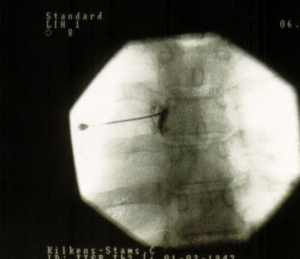

Para visualizar el sitio de punción se coloca el arco de fluoroscopia rayo en posición PA y se ubica en el centro de la imagen el espacio intervertebral del nivel que se desea alcanzar. Luego se mueve el arco de fluoroscopia en el plano axial para eliminar el doble contorno del borde inferior de la vértebra. Después de fijar el rayo se dan aproximadamente 25°-30° de inclinación oblicua hacia el lado que se va a intervenir, hasta que el foramen, que está por debajo del pedículo, se visualice como un círculo homogéneo. En esta imagen se apreciarán también las costillas y las articulaciones costovertebrales.

El punto de entrada se marca en el foramen que se visualiza debajo del pedículo, que sería el sitio de salida de la raíz. Se infiltra el punto de entrada con 5-10 ml de lidocaína al 1%. A través de este punto se avanza una aguja 22G de 10 cm, siempre en túnel visión. La aguja irá medial a la costilla y a la articulación costovertebral, y lateral al borde de la lámina.

Para confirmar la posición de la aguja se posiciona el arco de fluoroscopia rayo en lateral. Ésta debe alcanzar la región media o posterior del foramen en esta proyección.

Finalmente se rota el arco de fluoroscopia hasta la posición PA, la aguja no debe estar más medial de las 6:00 con respecto al pedículo. Se inyectan 1-2 ml de contraste para confirmar que la aguja está en la raíz , en la placa se debe observar la raíz dorsal y el espacio epidural.

Una vez confirmada la correcta posición de la aguja se procede a la radiofrecuencia (siempre pulsada en las raíces nerviosas) o al bloqueo con esteroides (metilprednisolona 20-40 mg o cualquier otro equivalente). El anestésico local es recomendado, aunque no se usa de manera universal.